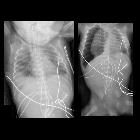

Mediastinalshift

bei asymmetrischer emphysematischer Überblähung. Rechts Röntgen, links CT zu einem anderen Zeitpunkt damals mit Infiltrat rechts.